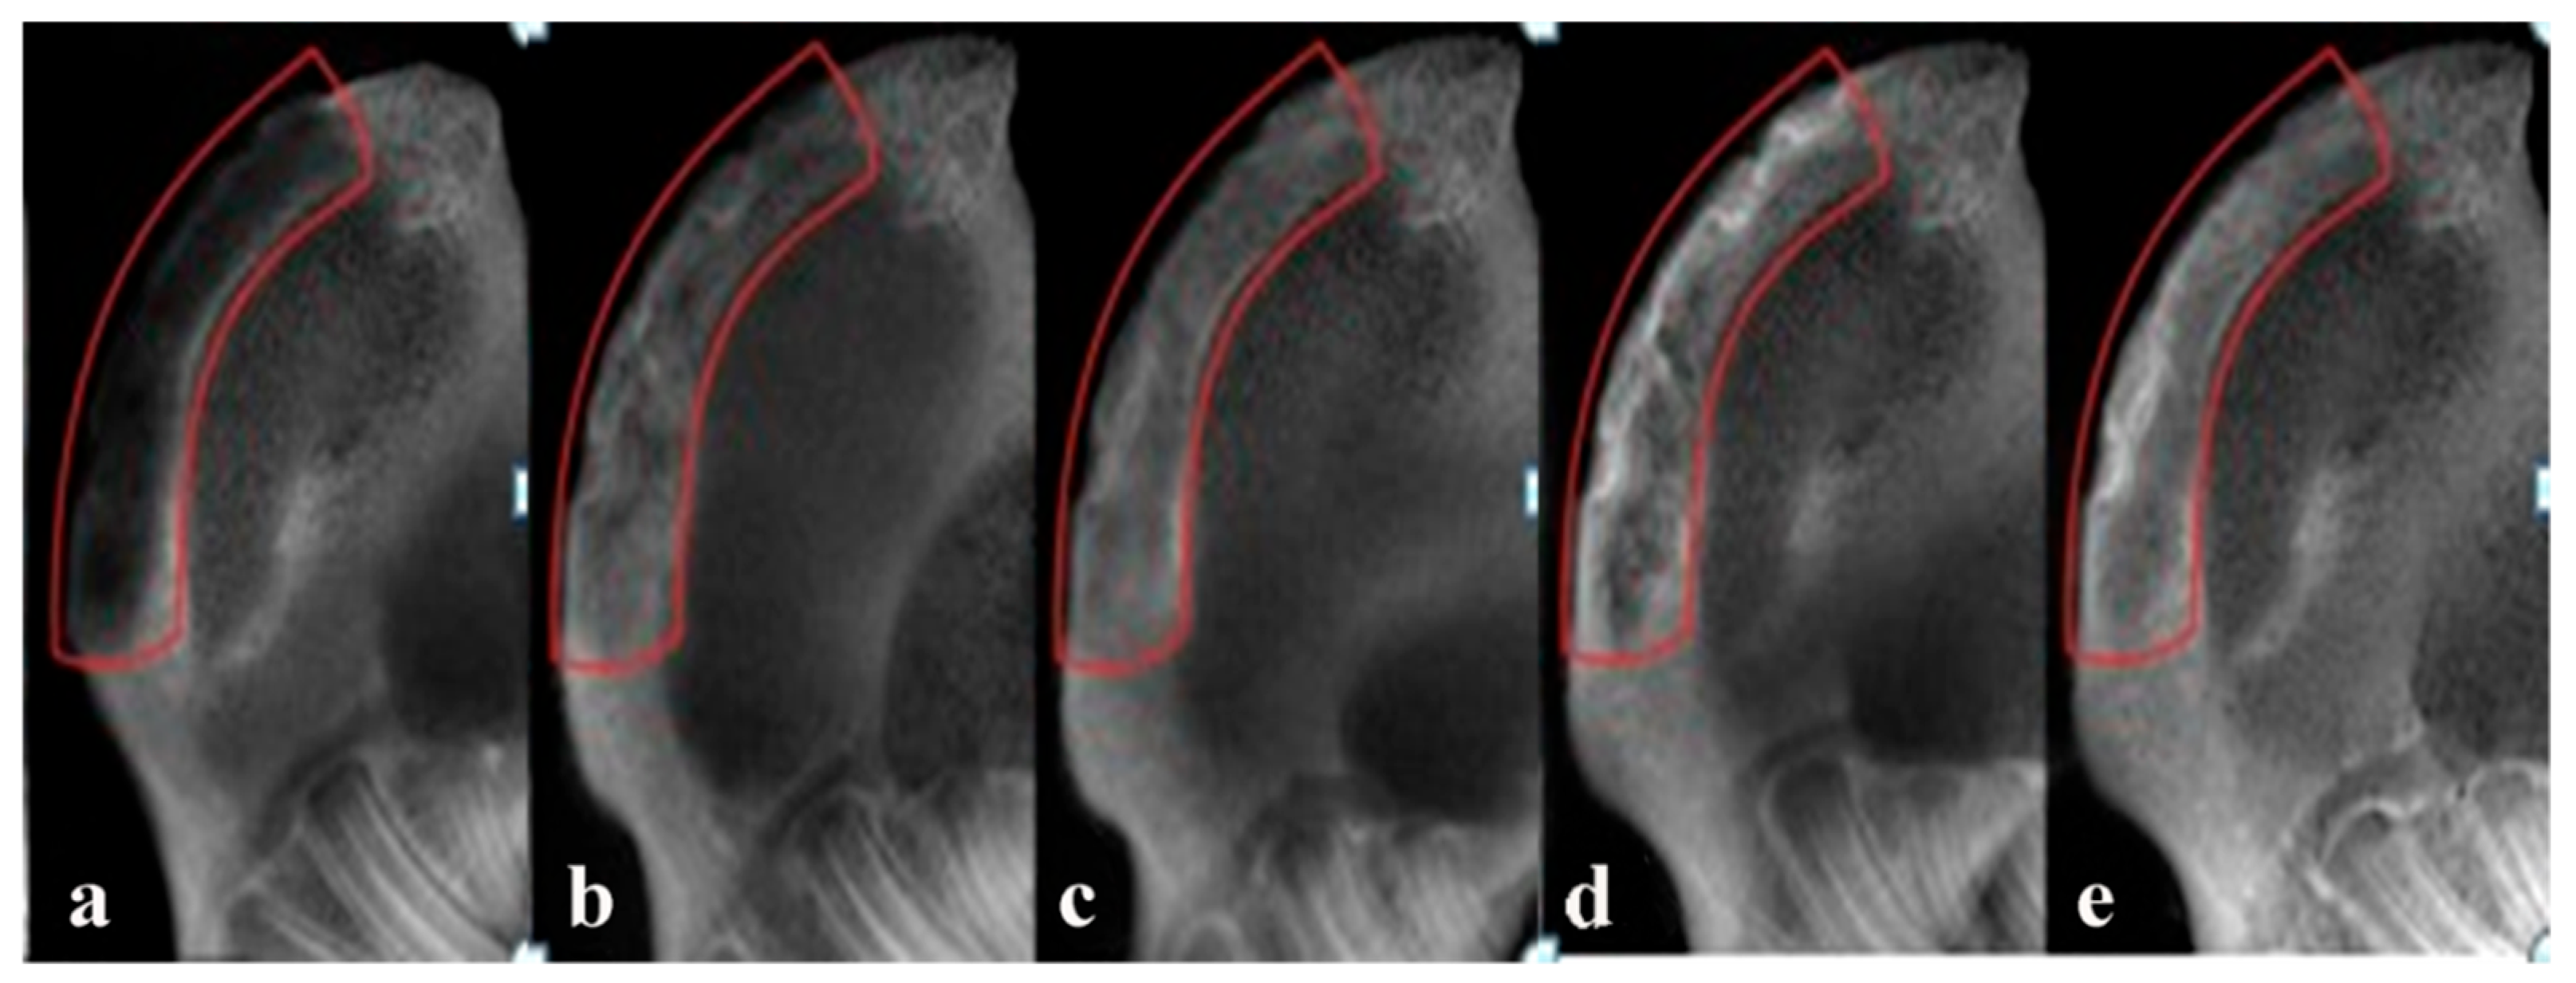

2.5. Radiographic Observations

3.4.1. Radiographic Observations